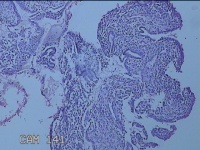

宫腔内容物

性别

女

年龄

47岁

临床诊断

1.异常子宫出血 2.慢性宫颈炎

一般病史

不规则阴道流血21天。

标本名称

大体所见

灰白暗红色不规则碎组织2.5x1.8x0.3cm一堆。

图3